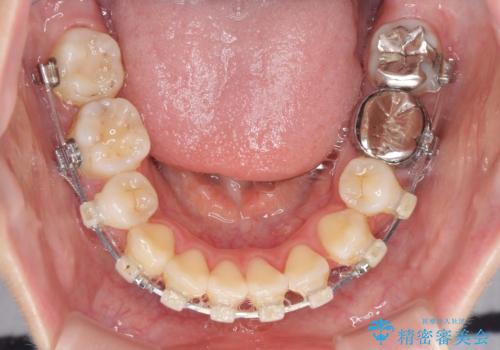

- ハーフリンガル

裏側矯正特有の抜歯スペースに前後の歯が倒れ込む状態が長く続き、改善に長期間を要しました。